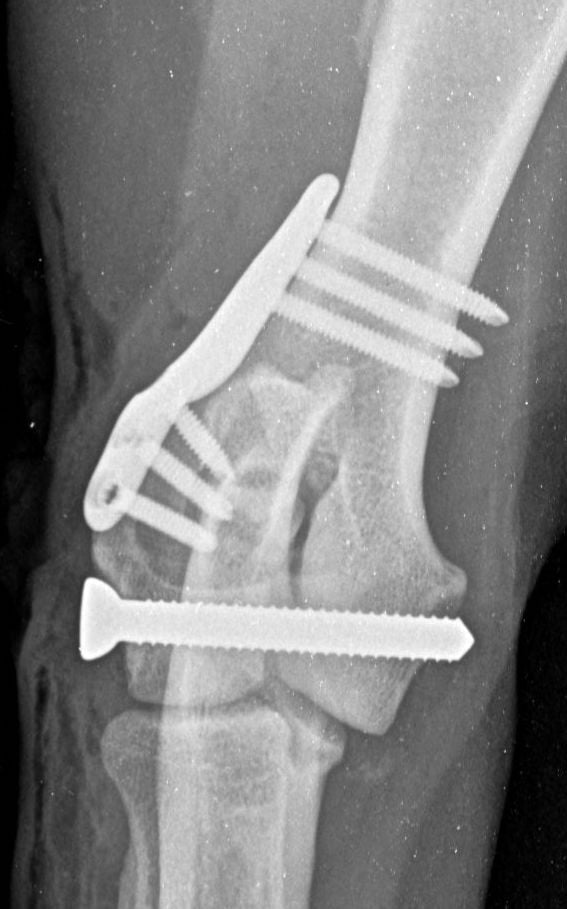

These concerns have led to recommendations being altered over the past decade or so, with veterinarians now using bone plates, instead of K-wires, as an adjunct to a transcondylar screw when managing humeral unicondylar fractures (Figure 2), even in puppies (Figure 3) (Clark, 2016; Kvale et al., 2022). However, the basis on which this conclusion for puppies was reached appears to have been flawed because it assumed that what had been shown to be the case for adults would also apply to immature patients. As the conclusion was felt to conflict with the author’s experience of treating such patients, a retrospective study was undertaken to evaluate complications and outcomes in immature dogs treated for humeral unicondylar fractures at one centre over a 10-year period (Butterworth, 2022). The findings of this study are summarised in this article.

Therefore, if the current trend towards the use of epicondylar plates, rather than K-wires/pins, in combination with a transcondylar bone screw to manage humeral unicondylar fractures in adults is also adopted for skeletally immature patients, we might well be throwing the puppy out with the bath water. The exception might be when the epicondylar ridge shows comminution, which means that a single K-wire might not provide enough stability, or when the patient shows prodromal lameness (both of which were noted in the patient related to Figure 3).